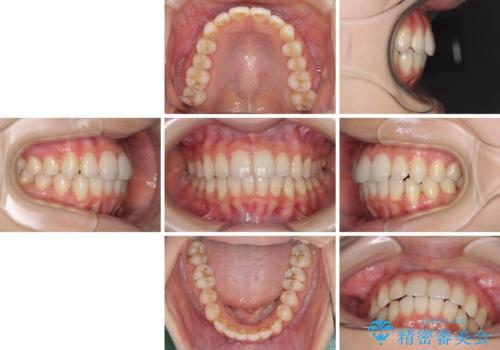

- 前歯のデコボコを気にして来院された患者様です。

叢生と捻転が随所に認められるものの、マウスピースで十分対応可能であったため、インビザラインにて矯正治療を行うこととしました。

マウスピース矯正は毎日しっかりと装着することがとても大切です。

こちらの方はしっかりと指示を守って装着してくださったため、予定通り治療を終えることができました。